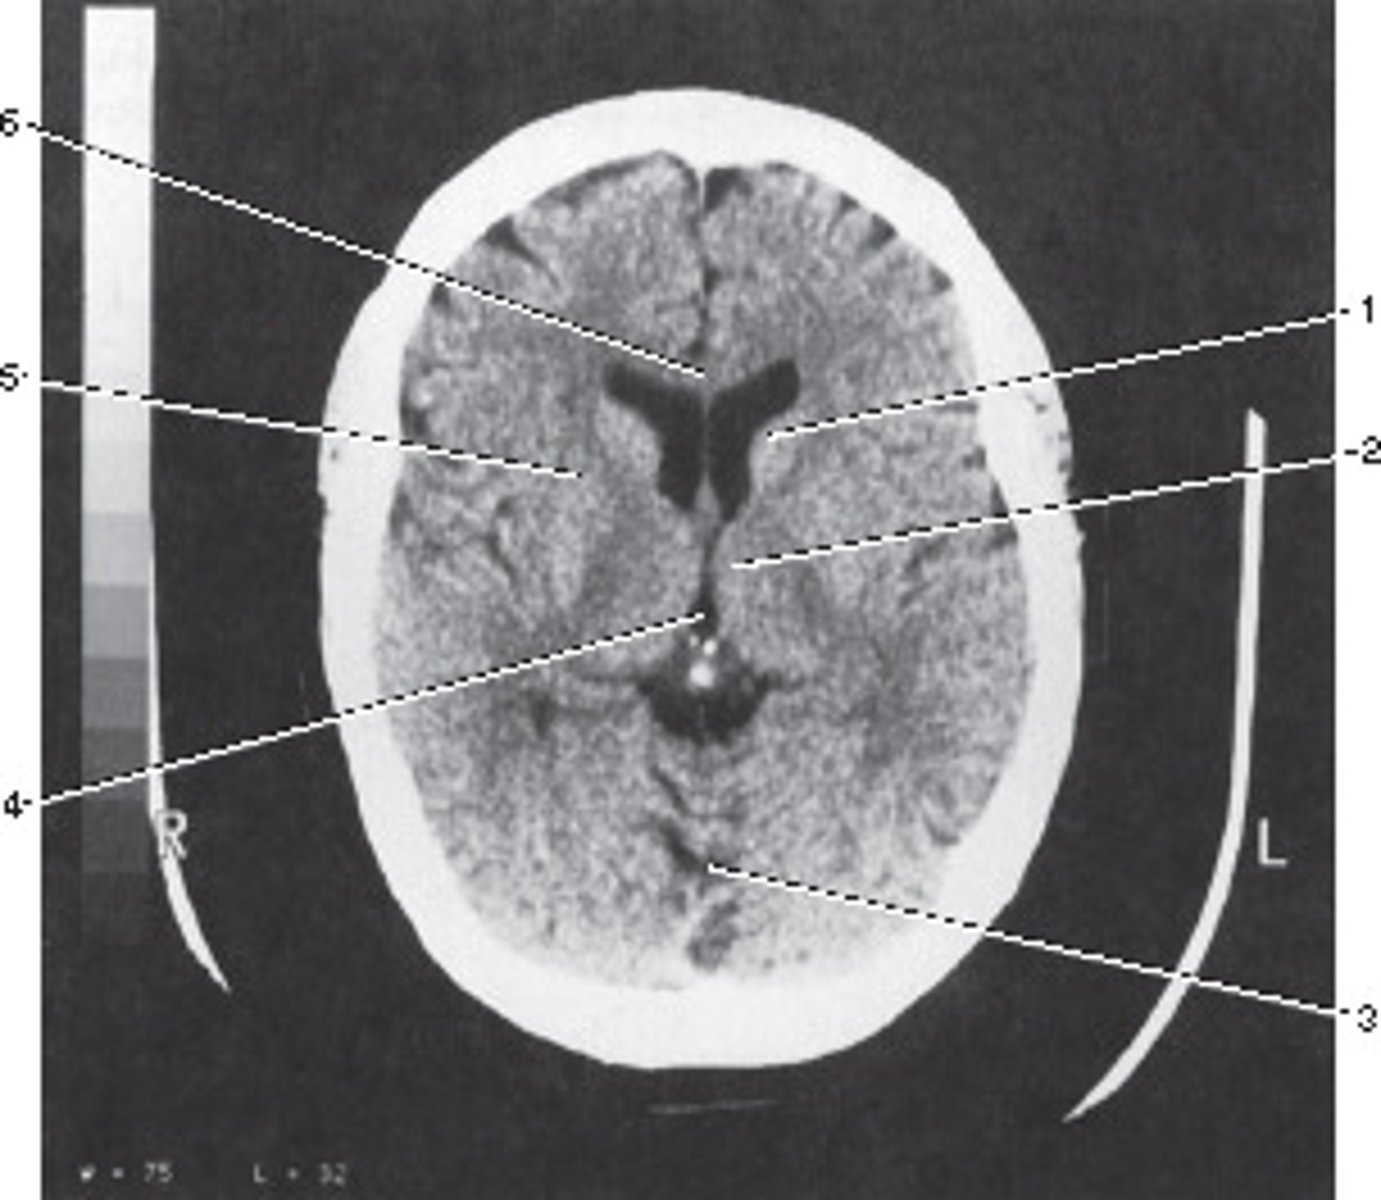

Third Ventricle

Number 4 corresponds to which of the following?

<p>Number 4 corresponds to which of the following?</p>

28

New cards

Genu of the Carpus Callosum

Number 6 corresponds to which of the following?

<p>Number 6 corresponds to which of the following?</p>

29

Axial

This image displays what anatomic plane?

<p>This image displays what anatomic plane?</p>